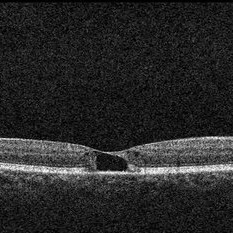

OCT OD Tamoxifen Retinopathy with Pseudocystic Foveal Cavitation in Tamoxifen Retinopathy

50-year-old female with breast cancer referred for CME had noticed gradual decrease in vision over the last 6-12 months; pseudocystic foveal cavitation due to tamoxifen retinopathy diagnosed by Dr. Hruby. Visual acuity cc 20/360, J16 OD and 20/40, J7 OS, normal IOPs, trace NSC OU. Bilateral pseudoholes noted on posterior segment exam without any retinal crystals. No leakage or tel vessels seen on the FA. Cystic cavitary alterations seen on the OCT with a large outer hole in the left eye. Plaquenil will be d/c.